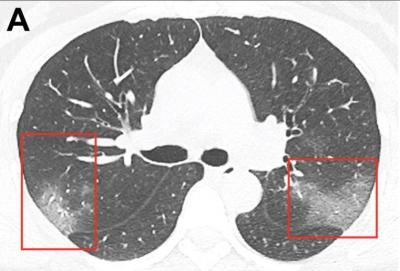

कोरोना वायरस फेफड़ों में सफेद धब्बे का कारण बनता है। रोगी के फेफड़ों में निमोनिया के लक्षण देखे जा सकते हैं। ये निशान कुछ में कम और कुछ में ज्यादा देखे जाते हैं।

कुछ रोगियों में, ये धब्बे फेफड़ों पर इस हद तक बढ़ते हैं कि फेफड़ों में वायुमार्ग अवरुद्ध हो जाते हैं। इसलिए, रोगी को अधिक ऑक्सीजन की आवश्यकता होती है। अक्सर मरीजों को वेंटिलेटर पर भी रखना पड़ता है।

इस फोटो में एक्स-रे को अलग तरह से देखा जाता है। जिसमें कोरोना वायरस के घाव पूरी तरह से दिखाई दे रहे हैं। सीटी स्कैन रिपोर्ट दाएं और बाएं ओर के फेफड़े को अलग-अलग वर्गों में विभाजित करती है और कई अंक देती है।